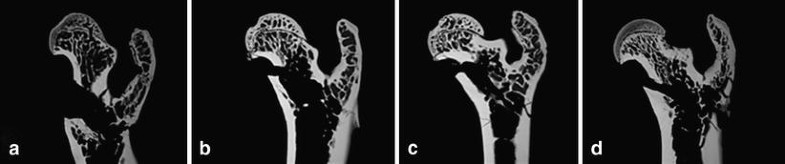

Microradiographs of the proximal femur of rat show the high content of both cortical and trabecular surfaces (after breaking test). a The control group (C) with a low trabecular density. b The rat femur after treatment with estradiol, c the sham group, and d after substitution with PTH (high trabecular content and thick cortical shell)

The mean of B.Dm/Ma.Dm ratio was in the PTH group (1.938) significantly higher than C group (1.716). The reason for this was mainly due to greater Ma.Dm in the C animals. The E (1.749) and sham (1.740) rats showed a higher B.Dm/Ma.Dm ratio than C but the results were not statistically significant (Table 1).

Histomorphometric changes after administration of estrogen and parathyroid hormone

After estrogen treatment, we did not observed any significant increases of the Tb.Ar, N.Nd/mm2 of proximal femur. In contrast, the PTH treatment induced a significant increase of trabecular bone area and connectivity compared to the C group. Although the B.Dm did not show any significant changes between the groups, the results of the B.Dm/Ma.Dm ratio demonstrated a significantly better outcome in the PTH animals. As there were not any significant changes concerning B.Dm, measured in the subtrochanteric region of all femurs, the better B.Dm/Ma.Dm ratios in the PTH rats seemed to be mainly caused by an increase in endosteal bone formation of cortex. This causes significantly lesser Ma.Dm in the PTH animals. The cortical changes that are normally difficult to evaluate could be reliably shown with the B.Dm/Ma.Dm ratio. These results, in addition to the results of fluorescence microscopy, provide useful information about intensity and localization (endosteal and/or periosteal) of bone remodeling (apposition) and drug influences within the cortical area. The increased bone formation rate was observed under PTH treatment both at the periosteal and endosteal side by fluorescent-microscopic analysis of the cross sections from the proximal femur. The endosteum here seems to be one of the targets of PTH with an accelerate bone formation and a pronounced filling in of intracortical cavities [8, 22].